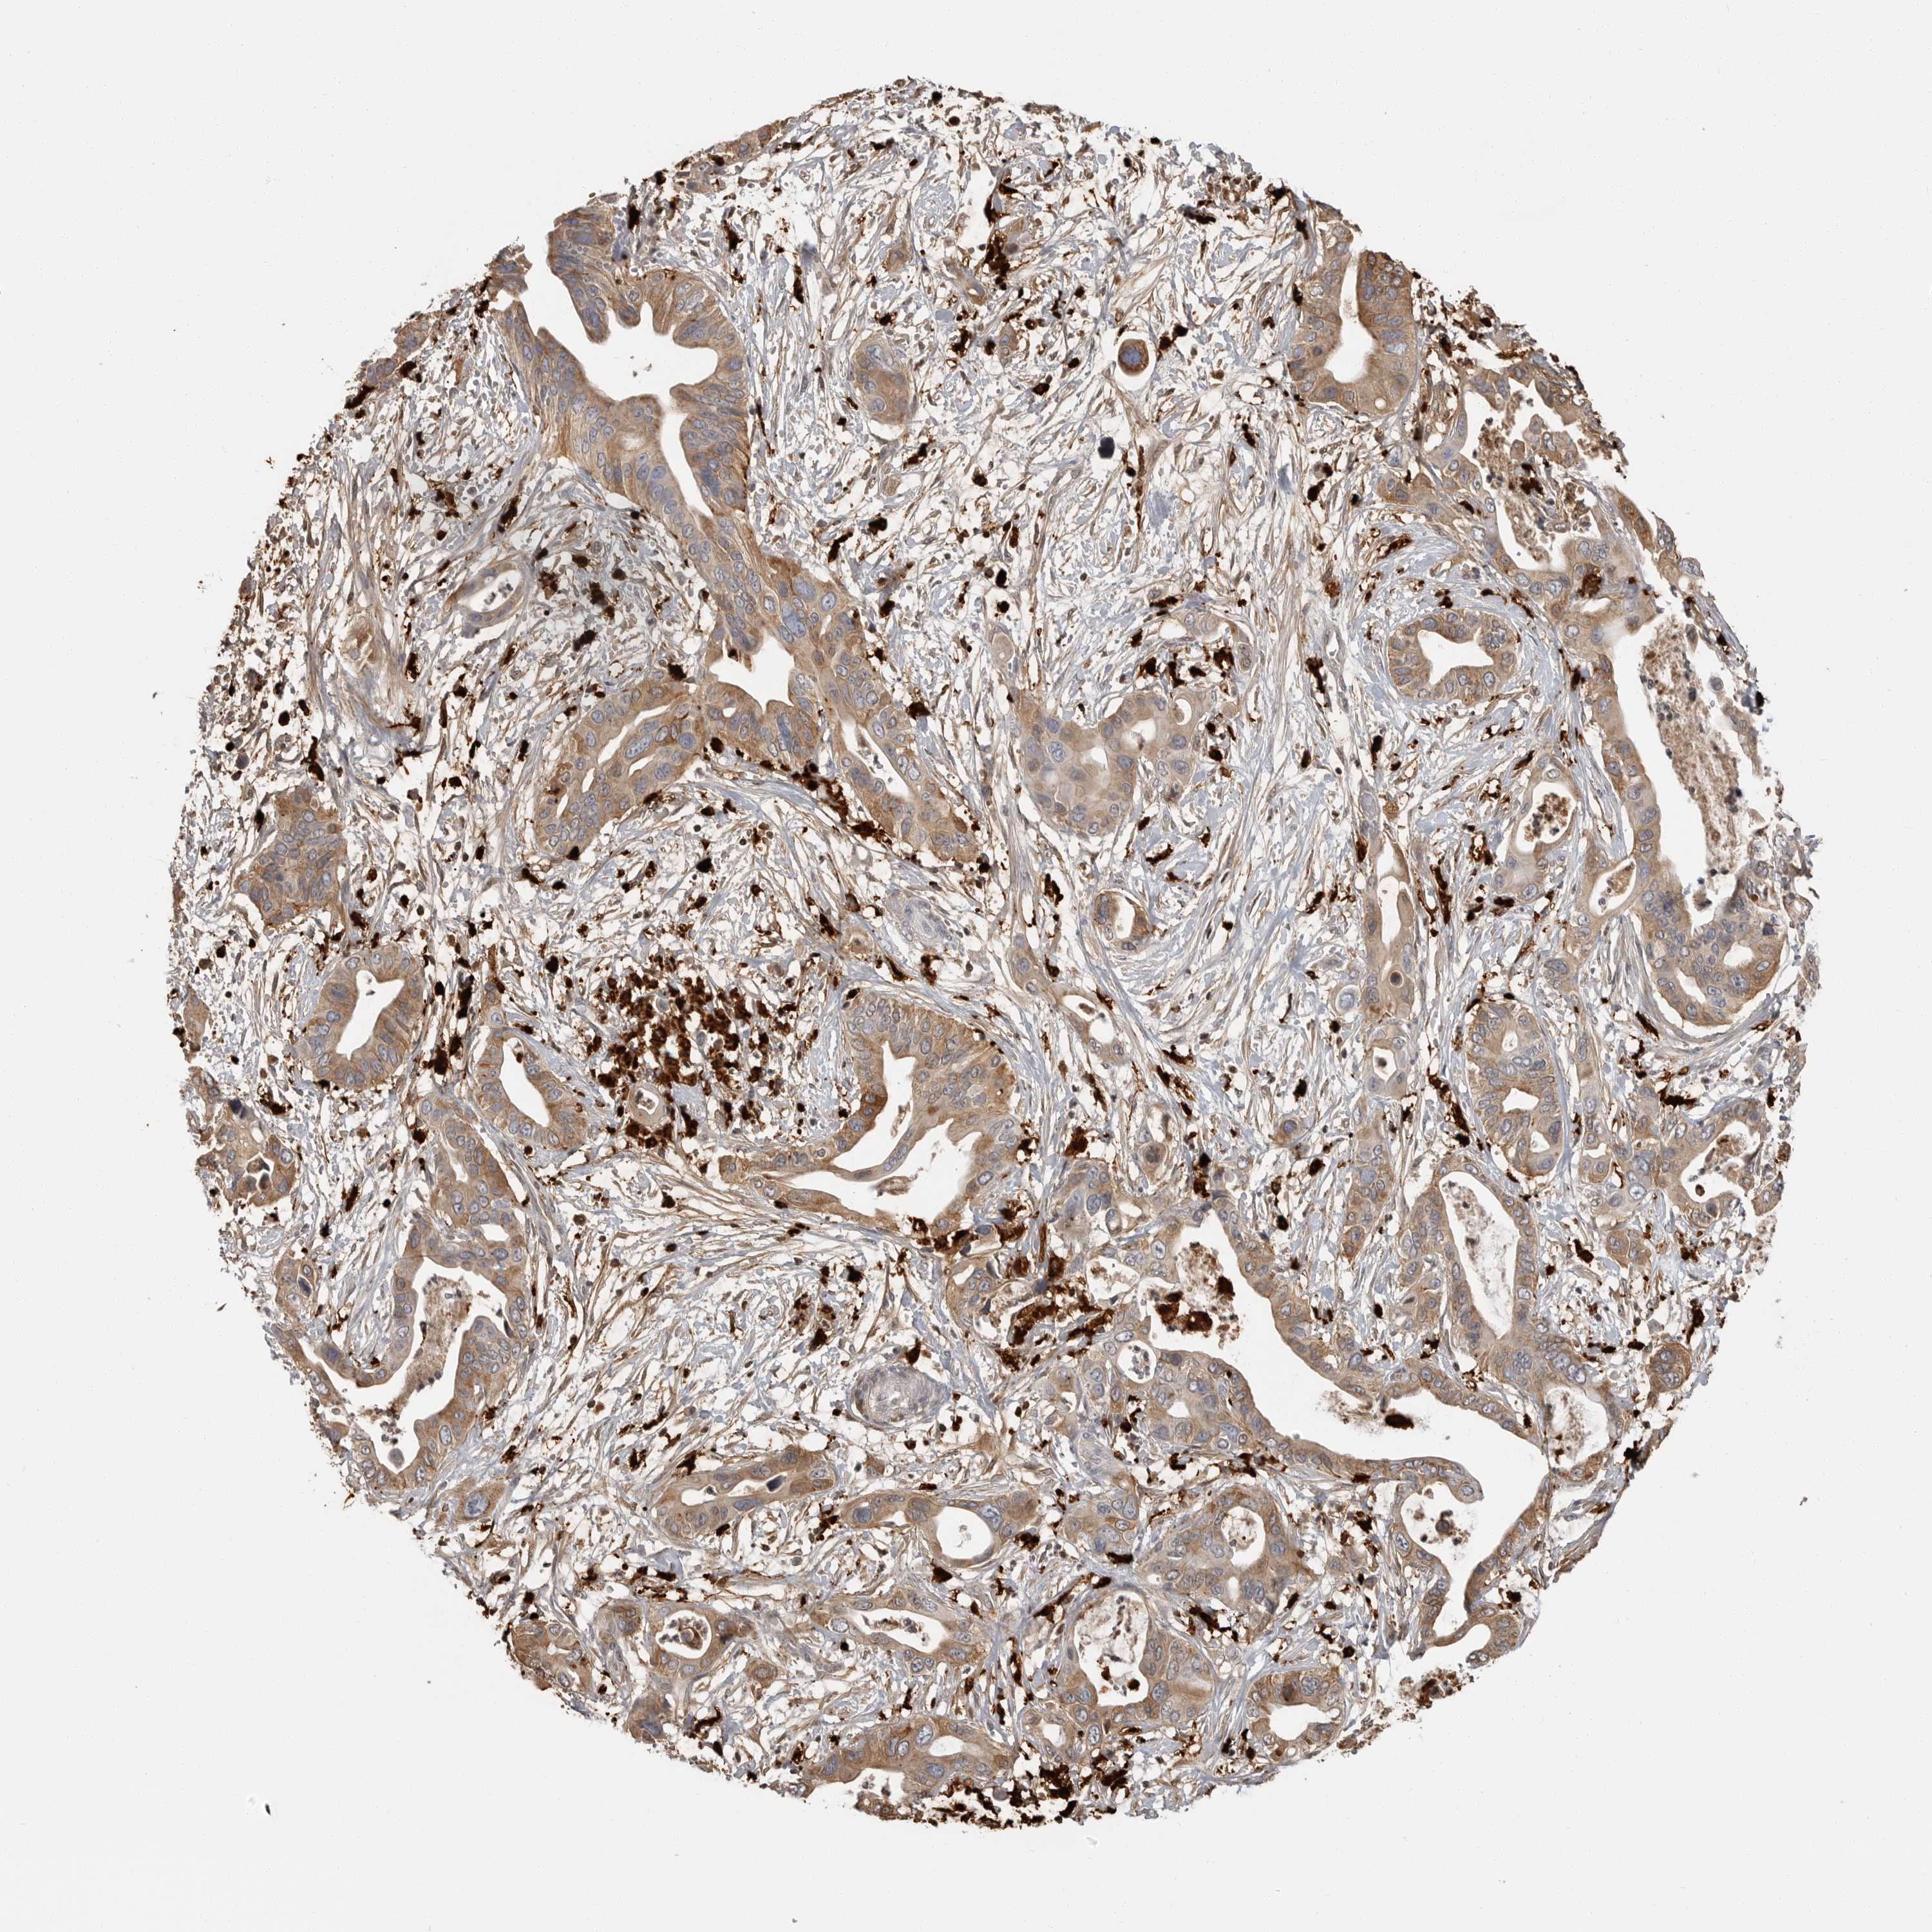

PANCREATIC CANCER - Protein expressioni

A mouse-over function shows sample information and annotation data. Click on an image to view it in a full screen mode. Samples can be filtered based on level of antibody staining by selecting one or several of the following categories: high, medium, low and not detected. The assay and annotation is described here.

Note that samples used for immunohistochemistry by the Human Protein Atlas do not correspond to samples in the TCGA dataset.

Antibody stainingi

Antibody staining in the annotated cell types in the current human tissue is reported as not detected, low, medium, or high, based on conventional immunohistochemistry profiling in selected tissues. This score is based on the combination of the staining intensity and fraction of stained cells.

Each image is clickable and will lead to virtual microscopy that enables deeper exploration of all samples and also displays staining intensity scores, fraction scores and subcellular localization as well as patient and tissue information for each sample.

Antibody HPA026650

Staining

High

Medium

Low

Not detected

Intensity

Strong

Moderate

Weak

Negative

Quantity

>75%

75%-25%

<25%

None

Location

Nuclear

Cytoplasmic/membranous

Cytoplasmic/membranous,nuclear

Adenocarcinoma, NOS